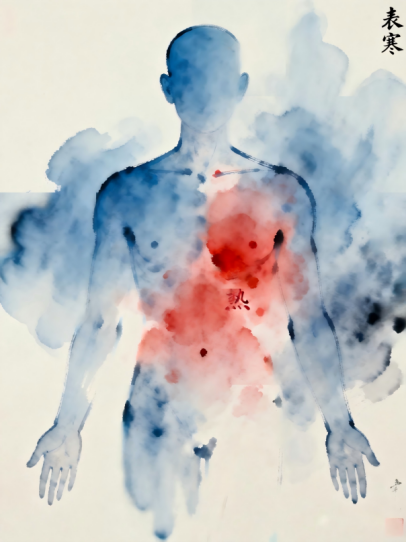

春节后的“寒包火”:身体在打架?春节团聚,盛宴连连。当满桌佳肴遇上节日欢聚,身体却可能发出令人困惑的“矛盾”信号:胃口大开却喉咙冒火,穿着厚衣仍后背发凉,头重腹胀,心里燥得慌。这种“冷热交织”的奇特感受,正是中医所说的“外寒内热”,俗称“寒包火”,好比冬天门窗紧闭却开着暖气的房间。

读懂身体的“矛盾语言”。这其实是春节特殊生活模式的写照。节日期间,脾胃超负荷运转,油腻煎炸的美食若运化不及,便易积滞生“热”,导致口咽干痛、便秘尿黄,仿佛体内有团“闷火”。同时,走亲访友、频繁出入,身体易受风寒侵袭,产生怕冷、头痛、肩背发紧等“外寒”表症。关键问题在于:内热想外散,却被外寒阻滞;外寒想透解,又受内热格拒。身体就这样陷入了“表里俱实”的困局。

破解之道,在于“双线作战”。面对这种里外夹击,单一地“清热”或“散寒”往往难以奏效。这就像房间既要开窗通风,又要调整暖气,必须双管齐下。中医应对此症的经典思路正是 “表里双解”。例如,源于古方“防风通圣散”的现代制剂防风通圣颗粒,其组方就体现了这一智慧:既用疏解之品帮助身体打开“窗户”散外寒,又用通泄之药为过载的消化系统“减负清仓”祛内热,同时兼顾调和扶正。当出现怕冷头痛与便秘口苦并存的典型“寒包火”症状时,这种同步处理表里问题的思路,就特别契合身体的实际需求。